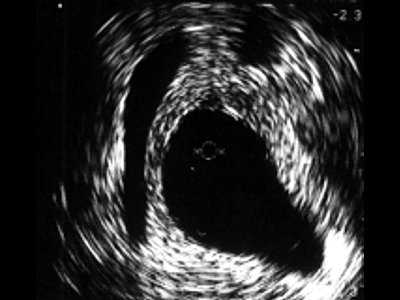

В мембранозном отделе (рис. 3) спонгиозная ткань не определяется, визуализируются повышенной эхогенности пластинка тазовой фасции, далее мочеполовая диафрагма с проходящими сосудами. При проведении датчика в область простатического отдела хорошо определяется предстательная железа, ее транзиторная, центральная, частично периферическая зоны, капсула.

Рис. 3. Эхограмма нормального мембранозного отдела мочеиспускательного канала.